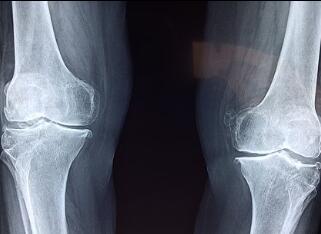

Мама посмотрела на успокоившегося сына и продолжила: «У всего, что имеет вредную сторону, будет другая сторона, которая будет полезна для людей. Нельзя сказать, что хорошо и плохо. Это зависит от того, как человек использует и где используется. Взрывчатка может причинить вред людям и взорвать гору для ремонта дорог. То же самое относится и к рентгеновским снимкам. Некоторые медицинские диагнозы, особенно в ортопедии, требуют рентгеновских лучей, чтобы определить, какие кости сломаны и где происходят переломы.